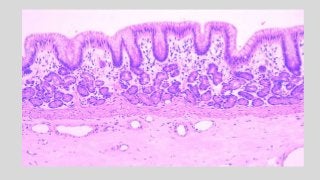

ESOPHAGEAL – GASTRIC JUNCTION

ESOPHAGEAL FEATURES

• Mucosa: Non keratinized stratified

epithelium

• Lamina propria: Mucous cardiac

glands, ducts, lymphatic tissue

• Muscularis mucosae: Single layer of

longitudinal smooth muscle fibers

• Submucosa and Muscularis Externa:

Similar in structure and continuous

with that of stomach

GASTRIC FEATURES

• Mucosa: Simple columnar

• Lamina propria: Filled with gastric

glands, gastric pits, lymphoid tissue.

• Muscularis mucosae: Double layer of

with that of esophagus.